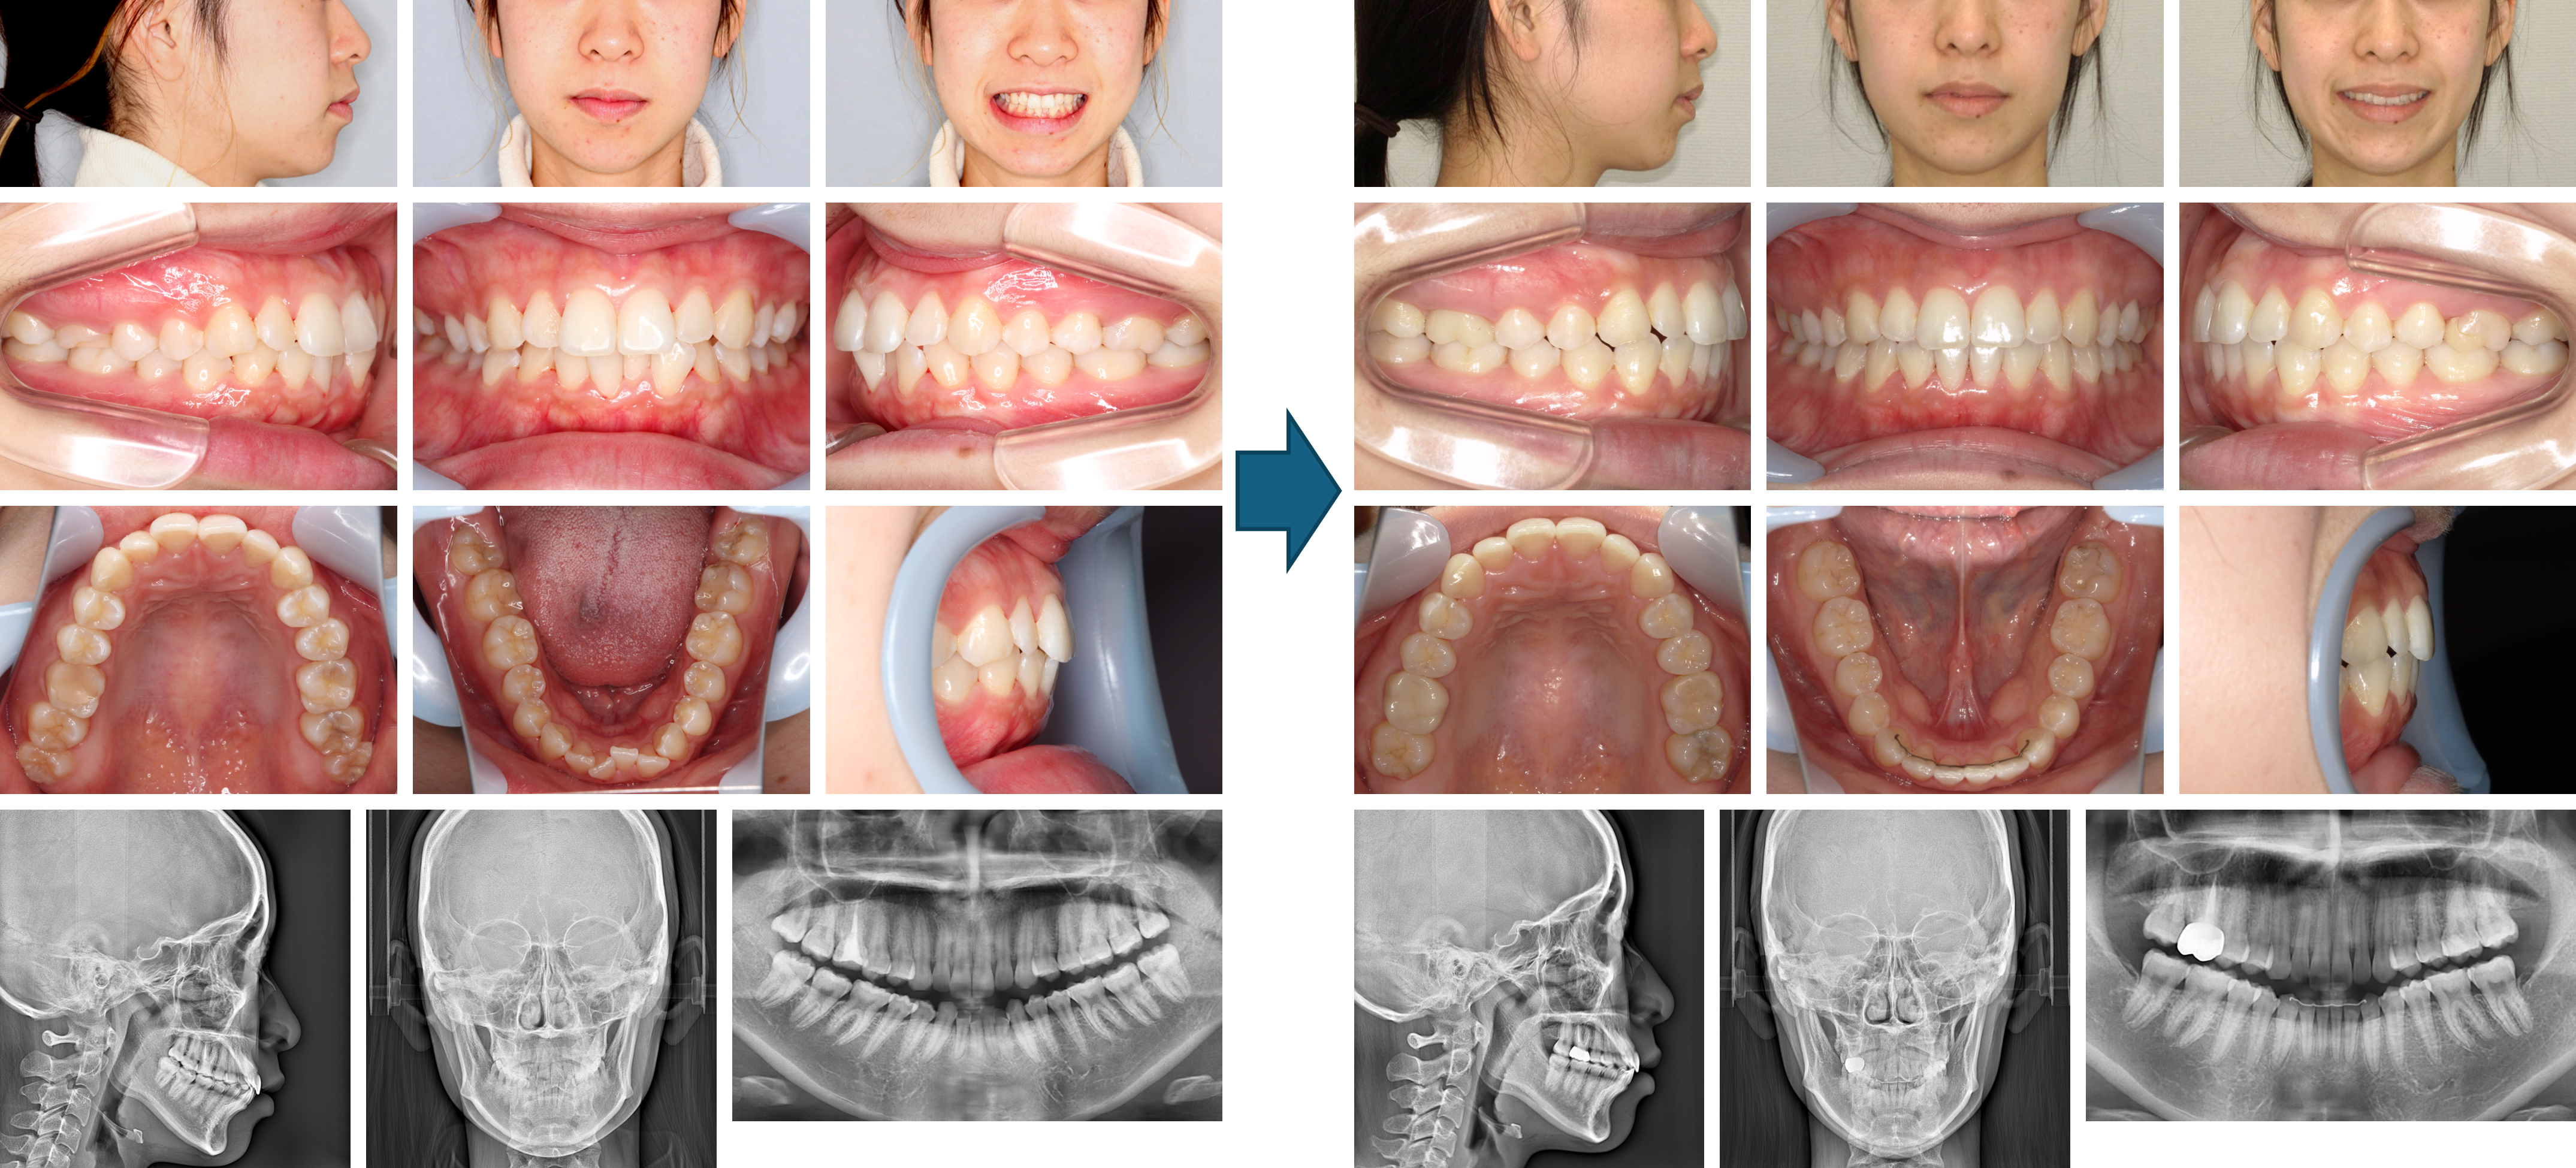

【治療例】初診時年齢:18歳8か月 / 性別:男性 / 主訴:上の歯のすきっ歯と出っ歯

本症例は、上顎前歯部の空隙と突出を気にして来院された。マウスピース型(アライナー型)矯正装置(インビザライン®)を用いて、上顎臼歯部の遠心移動とIPRを行いながら主訴の改善を図った。 その結果、上下前歯部間の距離は改善され、わずかであるが下顎の前方移動が認められた。

主訴:上の歯のすきっ歯と出っ歯

診断名:上顎前歯部にスぺースのある骨格性上顎前突症例

使用した主な装置:マウスピース型(アライナー型)矯正装置(インビザライン®)

抜歯/非抜歯および抜歯部位:非抜歯

※こちらの症例は2024年2月から2025年7月に行った矯正治療です(現在も経過観察中)

治療期間:1年5か月

治療回数:19回